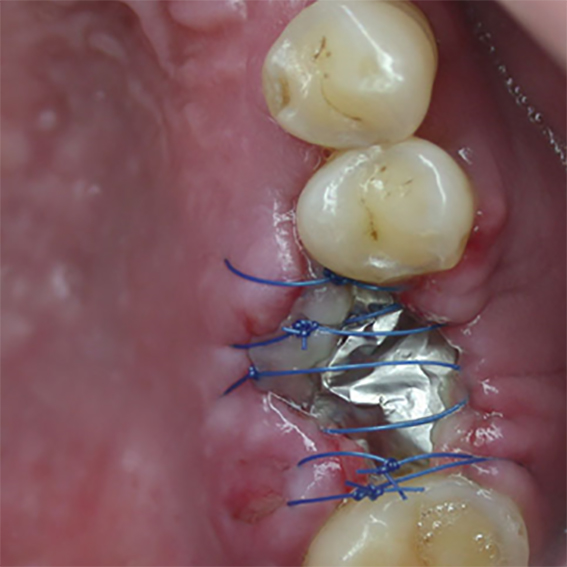

- No need for pin/screw fixation – immobilized by replaced soft tissue flap

- Primary would closure not necessary

- Excellent would healing underneath

Pure titanium membrane of ultra-thin thickness of about 10 microns (0.01mm). Totally inert, biocompatible and non-biological thus removing the fear of disease transmission from collagen of bovine source. It allows ease of handling and adaptation over the operative site. Because of its mouldability, it does not require pin or screw fixation, thus avoiding the risks of pin or screw swallowing or aspiration. Excellent clinical performance in guided tissue regeneration. Resistance to infection after exposure. Primary wound closure is not necessary. No tissue reaction or wound infection.